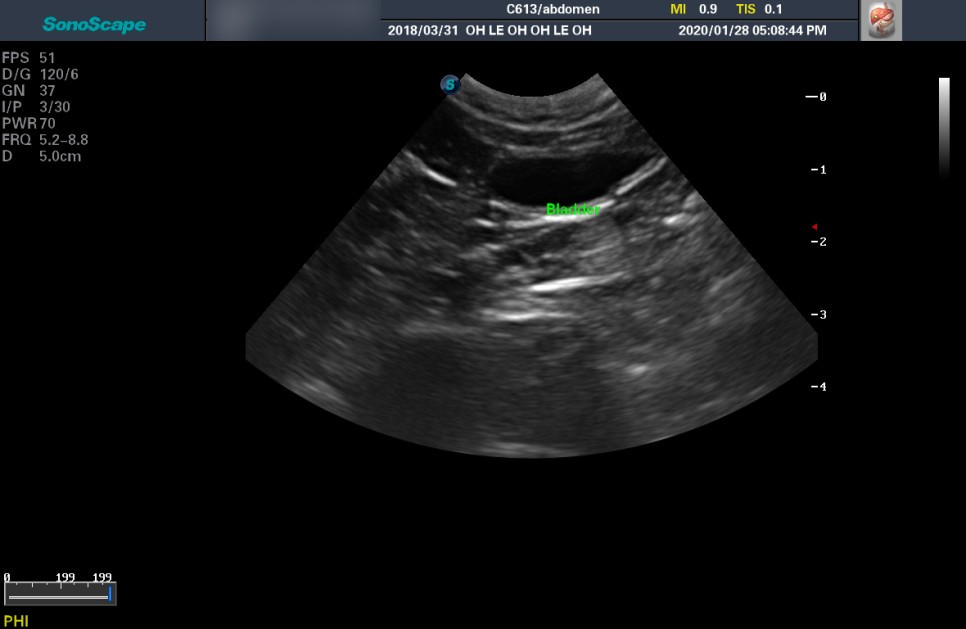

중성화 수술을 보냈을 때 들었던 복부 결절의 정체가 궁금해 여쭈었다. 흰 실타래가 엉켜있는 것 같은 모양의 염증 덩어리가 보였다고 전해 들었던 것을 말씀드렸다. 일단 복부 초음파와 X-ray를 찍어보자고 하셨다.

X-ray 상에서 다행히 복수는 없었다. 전체적인 염증은 아니라는 뜻이다. 하지만 동그란 결절이 여러 개 나왔는데, 정확하게 무엇인지는 알 수 없다고 하셨다. 아마 이것이 수술할 당시에도 보였던 것일 결절일터였다. 초음파까지 시행했는데 초음파 상에서도 비정상적인 소견은 없었다. 동그란 결절들은 초음파에선 보이지 않았다.